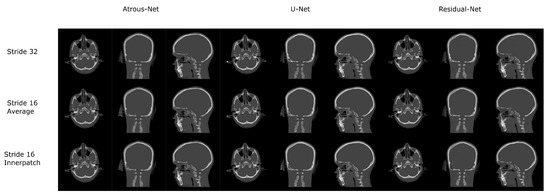

3.4. 3D Reconstruction Results

Figure 10 and Figure 11 show the results of the three merging strategies that have been tested: stride 32, stride 16 with averaging of overlapping voxels and stride 16 considering the inner cube. The average time to synthesize a volume is shown in Table 15 and Table 30. The first method—referred as “stride 32” in Figure 10 and Figure 11—generated artifacts in the boundaries of the cube and misalignment in the bone and air structures. Moreover, this approach showed a greater error than the other two in the quantitative results. Nevertheless, this method was quite fast, generating a volume in 8–19 s. The other two methods provided, in average, a similar quantitative result, being the use of the inner cube slightly better. However, the use of stride 16 increased the time to generate a pseudo-CT volume up to 58–90 s. According to the averaging strategy, some artifacts can be noticed in the boundaries of the cubes after a visual inspection of the results.

In this work, different ways of reconstructing pseudo-CT volumes from 3D patches were evaluated as well. According to our results, the best option would consist in using stride 16 and the inner cube of the patch. Compared to the averaging technique, the quantitative results were similar but the visual results (Figure 12 and Figure 13) showed less artifacts and aliasing effect in the boundaries of the patches when the inner patch is used. The only reason to use a direct merge of the patches using stride 32 would be real-time applications in which a fast reconstruction of the volumes is needed. However, the stride 16 scheme took around one minute to complete a volume, which is fairly low compared to acquisition times in MRI.

Figure 10. Comparison between the reconstruction method proposed.

Applsci 12 11600 g010

Figure 11. Comparison between the reconstruction method proposed.

Applsci 12 11600 g011